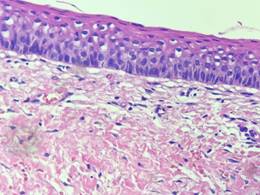

El examen histopatológico de la pieza quirúrgica confirmó definitivamente el diagnóstico inicial de quiste dentígero (Fig.9).

Histológicamente, los quistes dentígeros se caracterizan en la mayoría de los casos como una cavidad patológica, revestida por un epitelio plano estratificado5,9, donde en algunos casos específicos también se observa la presencia de una cápsula fibrosa de tejido conectivo laxo organizado, islotes o hebras de epitelio odontogénico, y un infiltrado inflamatorio de intensidad variable9, lo que es compatible con el espectro histopatológico de este informe de caso.